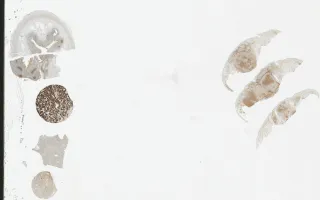

Histologically, the lymphoid infiltrate is morphologically consistent with centrocytes and few centroblasts. Architectural patterns have been described as either follicular, diffuse or mixed. PCFCL cells are CD20+. CD10+ and BCL-6+, BCL-2, which is commonly positive in extra-cutaneous follicular B-cell lymphoma is usually negative. CD21 usually highlights prominent follicular dendritic cell networks. Additionally, if molecular testing is performed, there is B-cell clonality present which helps exclude pseudolymphoma from the differential diagnosis.

This slide shows CD10 stain. See related content for H&E, CD20, and CD21 stains.